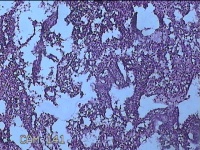

子宫腔内组织

性别

女

年龄

39岁

临床诊断

早期人工流产

一般病史

停经36天。

标本名称

大体所见

灰白暗红色不规则碎组织3x2.5x1.3cm一堆,未发现明显的绒毛样组织。

不具诊断价值。

在切片质量方面还需要加把劲。